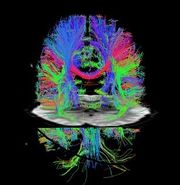

| 14:28, 31 December 2022 | Connectome1.jpg (file) |  |

35 KB | 1 | |